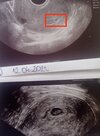

Dziewczyny dziś byłam na wizycie. Dwa tygodnie temu malutki pęcherzyk ciążowy, dziś zarodek 7mm, akcją serca 142 na minutę. Zdjęcia z USG w załączniku

• IMG_20220426_182619.jpg

IMG_20220426_182619.jpg

1,5 MB · Wyświetleń: 175